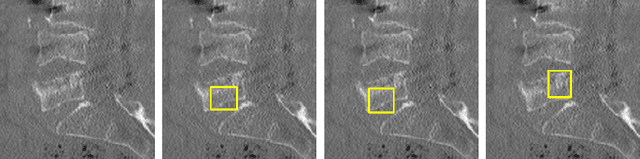

Abstract:Vertebral fracture grading classifies the severity of vertebral fractures, which is a challenging task in medical imaging and has recently attracted Deep Learning (DL) models. Only a few works attempted to make such models human-interpretable despite the need for transparency and trustworthiness in critical use cases like DL-assisted medical diagnosis. Moreover, such models either rely on post-hoc methods or additional annotations. In this work, we propose a novel interpretable-by-design method, ProtoVerse, to find relevant sub-parts of vertebral fractures (prototypes) that reliably explain the model's decision in a human-understandable way. Specifically, we introduce a novel diversity-promoting loss to mitigate prototype repetitions in small datasets with intricate semantics. We have experimented with the VerSe'19 dataset and outperformed the existing prototype-based method. Further, our model provides superior interpretability against the post-hoc method. Importantly, expert radiologists validated the visual interpretability of our results, showing clinical applicability.